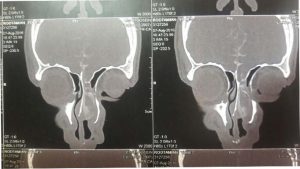

بسیاری از آن ها مادرزادی بوده و در حین کودکی تشخیص داده می شود. اما ناشی از ضربه نیز ممکن است روی دهد. از علائم این بیماری همچنین نشت مایع مغزی نخایی از بینی است. زمانی که این خروج این قسمت از مغز از طریق بینی تشخیص داده می شود نقش متخصصین رینولوژی تعیین کننده است که همچنان با روش های اندوسکوپیک می توان درمان موثر را مد نظر داشت. بیمار ما پسری ۲۰ ساله به جهت جراحی انحراف بینی و گرفتگی بینی مراجعه کرده است. در معاینه وی سابقه عفون پرده های مغز و بستری در ICU وجود داشت. وی سابقه ای از ضربه مغزی را متذکر نمی شود. تنها در خروج مایعی شفاف در سمت چپ بینی از کودکی شاکی بوده است. در بررسی مغز و اعصاب علامت خاصی نداشته و تنها وجود توده ای با رنگ صورتی کم رنگ در سمت چپ بینی مشهود بود. در ارزیابی های تصویر برداری شدرسی تی نمای توده ای یک طرفه با وجود یک نقص در کف قاعده جمجمه نمایان بود که در MRI نیز ارتباط این توده با مغز مشهود بود. بیمار کاند جراحی آندوسکوپیک برداشت این توده و ترمیم محل خروج آن و بستن این ارتباط به طور مادام العمر شد. که بعد از عمل نیز بیمار در طی بررسی شرح حالی از خروج مایع ذکر نکرده و انسداد بینی در آن سمت بینی باز شد.

در درمان کوتاه مدت بعد از تشخیص از مغز نوزاد سی تی اسکن تهیه می کنند تا به کمک آن بتوانند وسعت ضایعه و همچنین محل عمده ساختار های مغز و عروق خونی را تشخیص دهند . در این درمان برای نوزاد فورا انجام می شود و عمل جراحی ترتیب می شود .